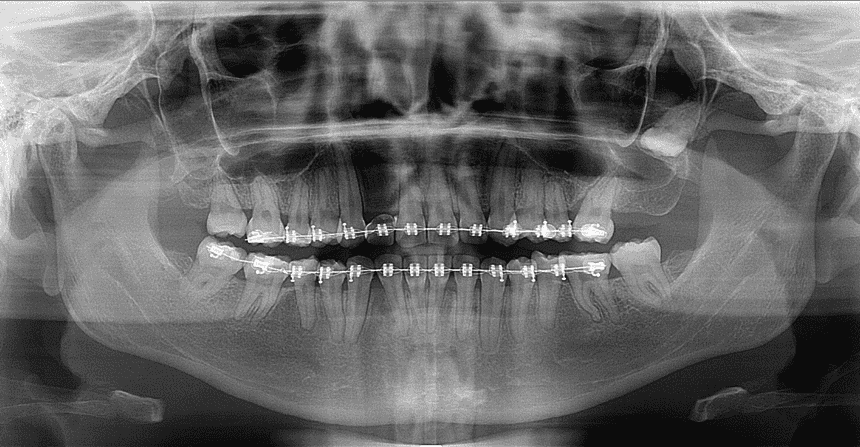

La radiografía panorámica dental es una técnica de imagenología fundamental en odontología que proporciona una vista amplia y detallada de toda la estructura oral. A diferencia de las radiografías dentales periapicales, que muestran áreas específicas de la boca, la radiografía panorámica ofrece una visión global de los dientes, mandíbulas, huesos faciales y otras estructuras adyacentes en una sola imagen.

o Dientes y Mandíbulas: Captura todos los dientes, tanto superiores como inferiores, y las mandíbulas en su totalidad.

o Estructuras Óseas: Incluye los huesos maxilares, la articulación temporomandibular (ATM), y otras estructuras óseas cercanas. - Imagen Panorámica:

o Vista General: Ofrece una imagen continua y amplia de la boca, lo que permite ver las relaciones entre los dientes y las estructuras óseas.

Estructuras Dentales:

o Carillas y Restauraciones: Se pueden evaluar carillas, coronas, puentes y otros trabajos dentales.

o Caries y Abscesos: Identificación de caries profundas, abscesos o infecciones.

• Mandíbulas y Huesos:

o Relación de los Dientes: Permite evaluar la alineación de los dientes y la relación entre la mandíbula superior e inferior.

o Estructuras Óseas: Visualización de quistes, tumores, y otras anomalías óseas.

• Articulación Temporomandibular (ATM):

o Desórdenes: Evaluación de posibles desórdenes o daños en la ATM, que pueden causar dolor y problemas de mandíbula.